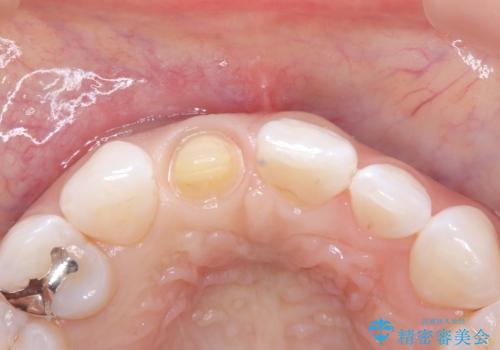

- 患者様は、前歯の被せ物の形や色が不自然で気になるというお悩みを抱えて来院されました。

診察の結果、既存の被せ物は古い素材で作られており、周囲の歯との調和が難しいことが分かりました。患者様とカウンセリングを重ね、アライナー矯正で歯列のガタツキを修正後、。より自然で審美的な仕上がりを目指してオールセラミッククラウンでの治療を提案しました。